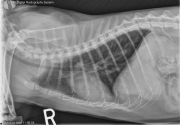

13 year old female neutered domestic shorthair cat with loss of voice for 6 months. Increased respiratory effort and stridor. How would you describe the lesion?

R LAT Thorax

There is lobular increased soft tissue opacity in the region of the larynx. The laryngeal tissues appear narrowed, and the air column is narrowed. The soft palate is mildly thickened. Within the thorax, the cardiovascular structures are normal in size and shape. There is a moderate diffuse bronchial pattern. The pleural space and mediastinum appear normal. Small osteophytes are present in the caudal humeral heads.

• Laryngeal mass – Neoplasia (carcinoma, lymphoma), fibrosis, edema less likely.

• The bronchial pattern may be secondary to chronic lower airway disease which may have infectious and noninfectious inflammatory components.

CT showed a poorly enhancing mass of the left retropharyngeal wall. An endoscopic examination with biopsy of the mass revealed large cell lymphoma. An additional mass was found at the ileocolic junction. The patient responded to chemotherapy well with relapse after 8 months.